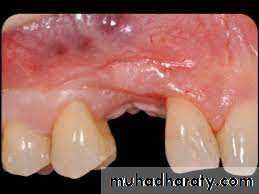

6- Gingival recession of one or more mandibular incisors.7- Split maxilla.

Why?1- It prevent proper cleansing of all surfaces of teeth.

2- Cause dental decay.3- Increase the chance of gum disease.

4- Prevent normal function of the teeth.